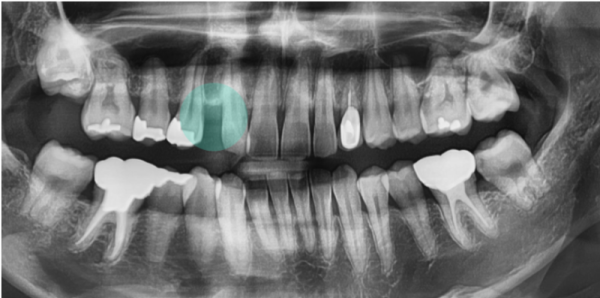

이 환자분은 송곳니 1개가 없는 상태이기도 했습니다.

결손치였는데요. 임플란트를 심어서 치아의 건강을 지켜야 하는 상황입니다.